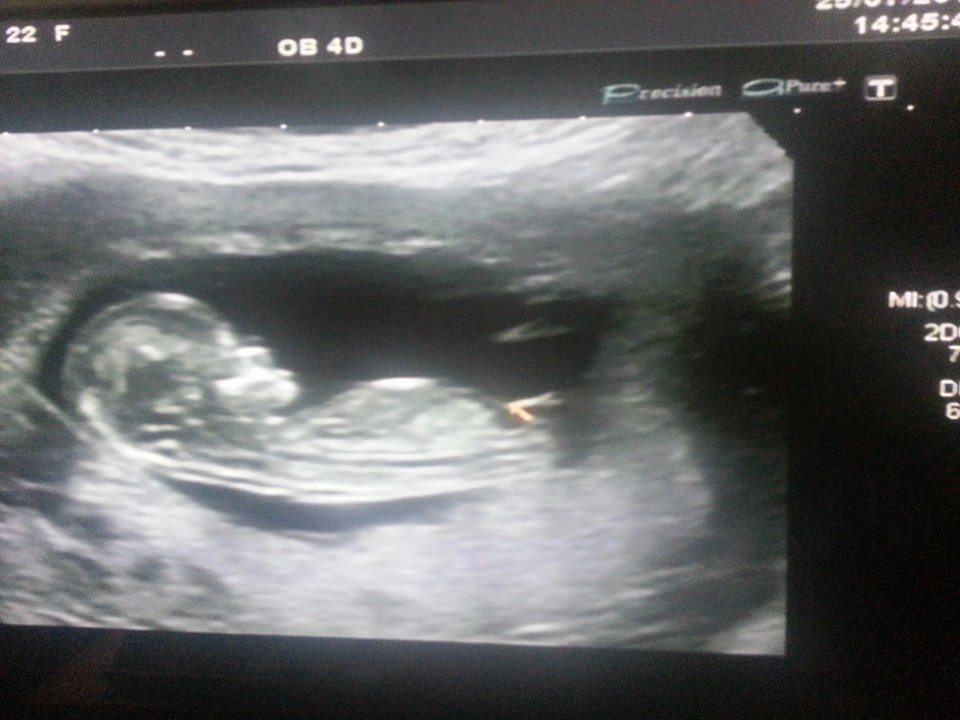

The Echo is taken by 11+6 weeks, im today 12 weeks.

girl

Girl except 2nd from the bottom looks boyish.

I feel it's too early to guess. If pushed I'd lean girl but it may still have time to rise so it's a very cautious girl lean from me. GL! Hope it's whichever gender you wish for :)

It's too early and seems to angle up slightly even this early which would make me lean boy but it also very long which makes me leans girl...so idk!!!

I'm guessing boy

Boy